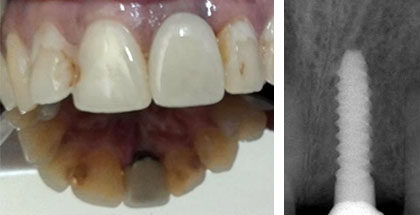

Se chequeó clínica y radiológicamente a la paciente a los 15 días, al mes y a los 3 meses de la intervención; y al cumplir los seis meses de la implantación se procedió a la rehabilitación definitiva del caso con corona metalcerámica consiguiendo una rehabilitación estética, funcional y biomecánicamente estable, lo que coincidió con las expectativas del paciente (Fig. 3).

Fig 3 . Rehabilitación definitiva metalcerámica y control radiográfico de la osteointegración.